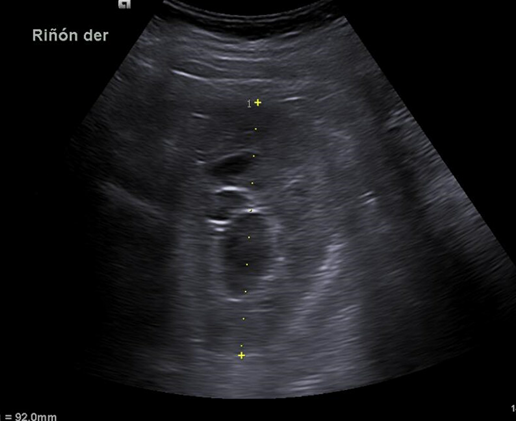

Hallazgos ecográficos

Riñón derecho 9,9 cm con morfología y ecogenicidad conservada. Presenta hidronefrosis grado III. No se identifica causa obstructiva.

Se remite a la paciente a Urgencias donde fue dada de alta con diagnóstico de CRU y tratamiento con Fosfomicina. Consultó al día siguiente, persistiendo el dolor y febrícula, remitiéndose de nuevo a Urgencias. Solicitan estudio de imagen con ecografía y ante los hallazgos se amplió el estudio a TC simple de abdomen: Hidronefrosis grado III con líquido perirrenal sugestivo de rotura de fórnix. Nefrolitiasis puntiformes en ambos cálices inferiores. Sin clara causa obstructiva objetivable. Se contactó con Urología de guardia quien propuso tratamiento ambulatorio con seguimiento posterior y colocación de nefrostomía programas y pielografía para estudio de probable estenosis de unión pieloureteral. Actualmente la paciente permanece en seguimiento por urología.